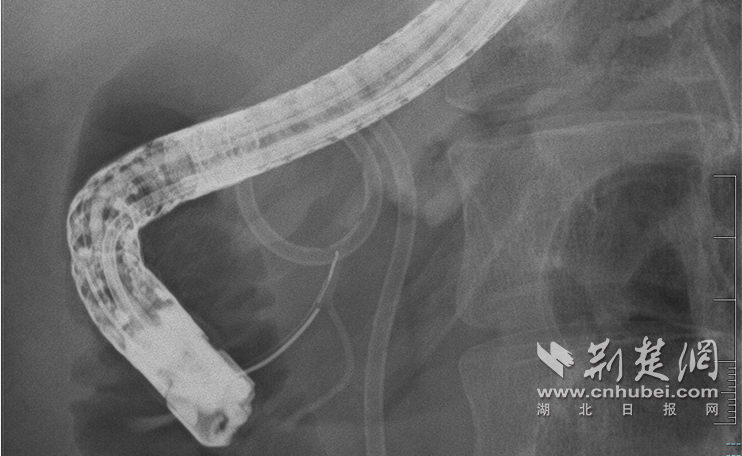

该图像显示了 m内镜下微创修复破裂胰管

面对这个问题,大家决定迎难而上,在内镜下对破损的胰管进行最低限度的修复。 10月30日,术中造影清楚显示病情的复杂性:胰头胰管弯曲,胰管颈部完全断裂,形成直径约2厘米的囊肿,远端胰体、尾部胰管因梗阻而轮廓明显。

Aof的技术难点在于空间定位。在医疗队员的密切配合下,覃华和罗振龙副主任医师在X光引导下小心翼翼地将导丝穿过囊腔,准确找到远端导管细如发丝的开口,实现了断导管的“交会成功”!随后,专家成功置入支架并恢复正常。建造了他的胰液引流通道。